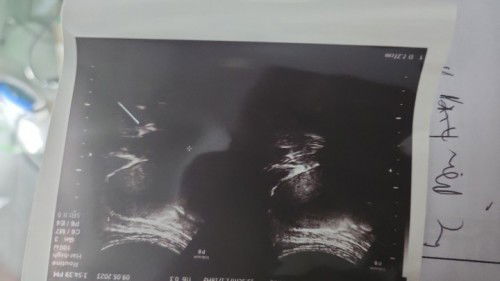

Mlm dok jika hasil usg seperti ini artinya apa ya?

Mohon penjelasannya dokter